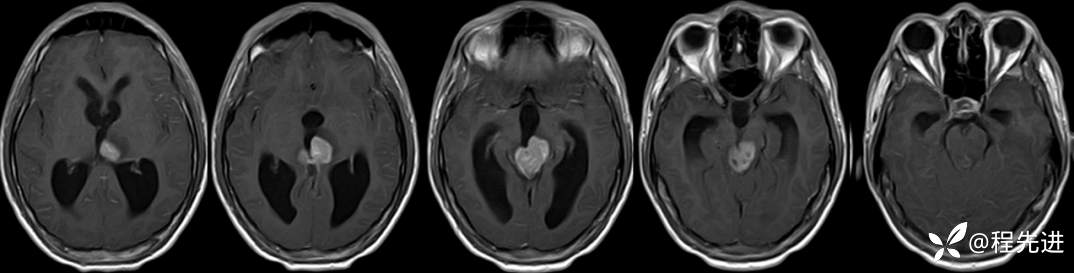

MRI平扫+增强:

FLAIR:

T1增强: